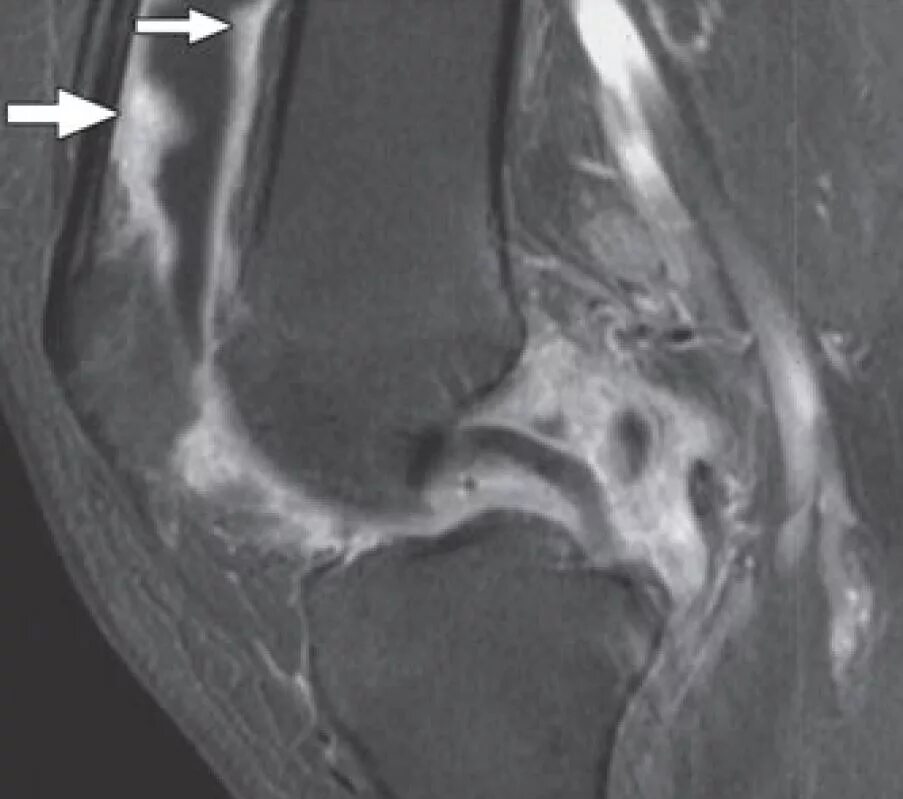

Что такое синовит коленного сустава на мрт